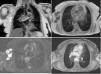

A 77-year-old female presented to our clinic with a mass in the right axilla. Coronal (Panel A) and axial (Panel B) T2-weighted MR images reveal a multiseptated cystic lesion solely in the right axillary fossa. Axial pre- (Panel C) and post-contrast (Panel D) T1-weighted MR images show multiple cysts with peripheral enhancement of their walls following gadolinium administration.

Although extremely rare, clinicians should include hydatid disease in the differential diagnosis of palpable axillary mass lesions in endemic regions.